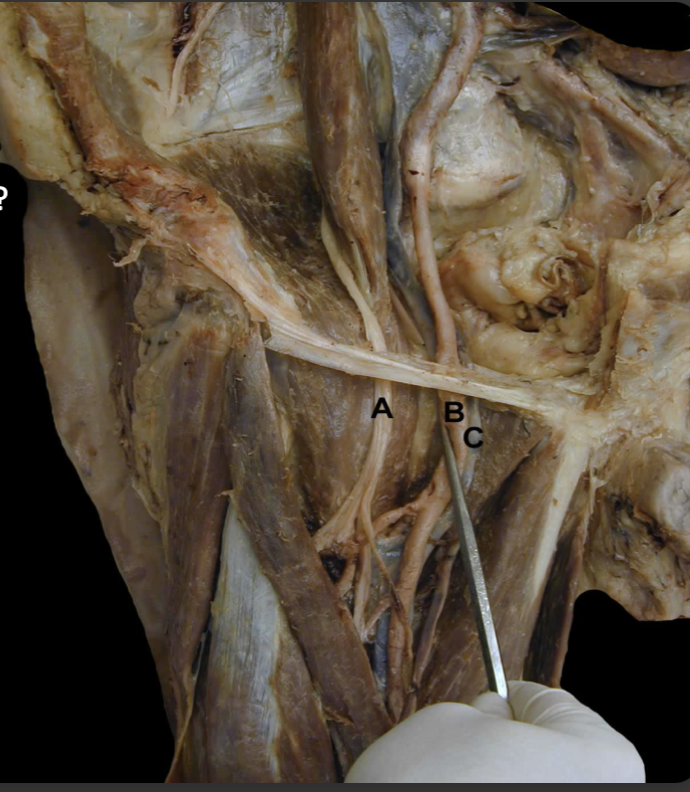

<p>Try and Identify the nerves and nerve roots of he <strong>Lumbarsacral Plexus&nbsp;</strong></p>

Try and Identify the nerves and nerve roots of he Lumbarsacral Plexus

A: Iliohypogastric n (L1)

B: Ilioinguinal n. (L1)

C: Lateral Cutaneous n. of the Thigh (L2-L3)

D: Femoral n. (L1-L4).

E: Geniofemoral n. (L1-L2)

F: Obturator n. (L2-L4)

G: Lumbosacral trunk (L4-L5)

H: Sciatic n. (L4-S3)

I: Genitofemoral n. (L1-L2).